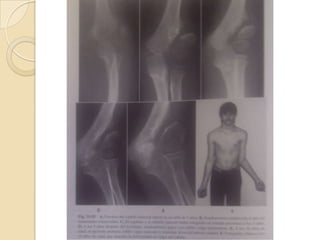

Neer y Horowitz clasificaron las fracturas del tercio proximal según en grado de desplazamiento. Y las fracturas con gran desplazamiento necesitaban reducción cerrada seguida de alguna forma de tracción o enclavado percutáneo.Se concluyo que el tratamiento no quirúrgico en fracturas de humero proximales era   recomendable hasta niños de 15 años

Neer y Horowitzclasificaron las fracturas del tercio proximal según en grado de desplazamiento. Y las fracturas con gran desplazamiento necesitaban reducción cerrada seguida de alguna forma de tracción o enclavado percutáneo.Se concluyo que el tratamiento no quirúrgico en fracturas de humero proximales era recomendable hasta niños de 15 años